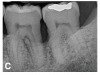

(6.) Initial periapical radiograph taken on November 15, 2015, showing infrabony defect approaching the apex of the distal root of tooth No. 19, on which there was a calcified mass (hypercementosis) and evidence of furcal bone loss. The entire distal root of tooth No. 18 appeared to have no bone support, and a small arrested carious lesion was noted on the distal crown of tooth No. 18. Teeth Nos. 17 and 18 were initially given a hopeless prognosis and slated for extraction.

Figure 6

A 63-year-old male patient with a medical history of asthma, hay fever, sinusitis, and arthritis was referred for periodontal therapy in November 2015. He reported taking multivitamins, fish oil, and naproxen sodium occasionally for pain. The patient did not report experiencing any dental discomfort. The clinical findings, radiographic interpretations, diagnosis, and preoperative prognosis for teeth Nos. 17 through 19 are summarized in Figure 6 and Table 1. The patient was informed that teeth Nos. 17 and 18 should be extracted and that tooth No. 19 would need regenerative therapy. A treatment plan was devised for phase I and phase III periodontal therapy, and the patient consented to the proposed treatment verbally and in writing.

The patient's periodontal disease improved with initial nonsurgical periodontal therapy that involved scaling and root planing. This initial treatment was followed by only SPT every 3 months. Despite treatment, residual deep periodontal probing depths remained, so a decision was made to maximize improvements with nonsurgical therapy and to reassess as needed to determine whether surgical intervention was appropriate. After almost 5 years of SPT and good patient compliance with plaque control and supportive care, the periodontium was stable. Because of the resulting bone formation and improvements in clinical attachment levels (Figure 7 through Figure 13), it was determined that periodontal surgical intervention was not necessary.

In the case report presented, treatment with nonsurgical therapy for 5 years effectively halted destruction and led to bone regeneration and improved clinical attachment levels. Although the primary etiology of periodontal disease is well documented, secondary etiologic and contributing factors are numerous.16 After initial therapy in the current case, there was radiographic evidence of a hypercementosis-like lesion on the distal root of tooth No. 19 (Figure 7 through Figure 10). Hypercementosis is a nidus for plaque accumulation leading to disease progression; however, the presence of this lesion did not explain the disease severity observed for tooth No. 18. Chronic periodontitis is the most widespread form of periodontal disease, and nonsurgical periodontal therapy is the most common type of therapy.17 Scaling and root planning is the gold standard for periodontal treatment. When performed meticulously, they result in improvement of clinical parameters through changes related to tissue shrinkage, long junctional epithelium, new attachment, and in rare circumstances, regeneration.18 The use of nonsurgical periodontal therapy for treatment of periodontal disease requires that the timing for re-evaluation is customized for each patient. Because individuals heal at different rates, the overall medical condition, nutritional intake, environmental and social risks factors, local factors, and colonization of pathogenic bacteria of patients should be considered.7,8 Some patients cannot afford, or choose not to pursue, surgical periodontal therapy. For these patients, clinicians should delay surgical decisions until periodontal risk factors are addressed and nonsurgical efforts are exhausted.